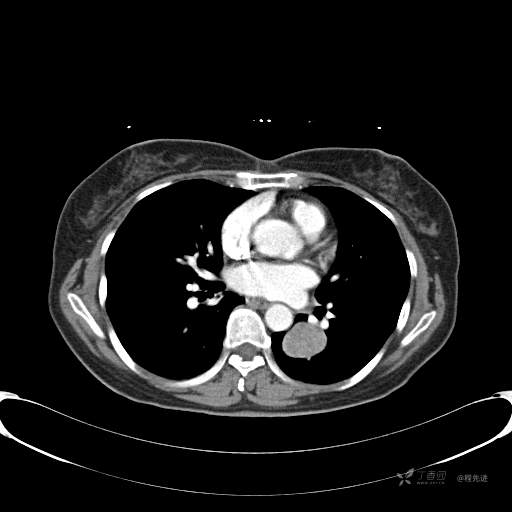

6月特别精彩病例|中老年女性,体检发现左肺下叶肿块,期待你的精彩演绎【病理公布】

患者性别:女

患者年龄:57岁

简要病史:体检发现

CT增强

平扫CT值约40HU(未上传图像),增强后动脉期CT值约70HU,静脉期CT值约97HU。

肺硬化性血管瘤 (20)